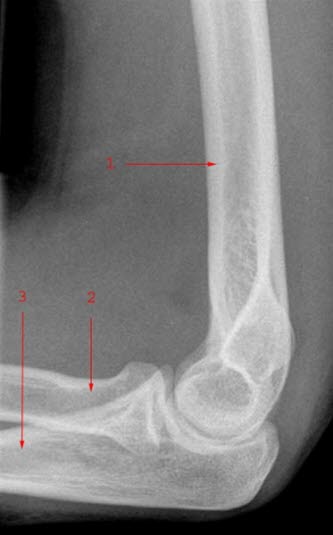

Gode røntgenbilder forutsetter at området som avbildes holdes i ro. Som regel er det nødvendig å ta bilder fra minst to retninger for å få en tilfredsstillende fremstilling av beinet. Vanligvis tas disse vinkelrett på hverandre - vanligvis forfra/bak og sidebilde (jfr. albue front og albue side nedenfor). Mer detaljert informasjon om et bein vil kunne kreve flere projeksjoner, f.eks. skråbilder.